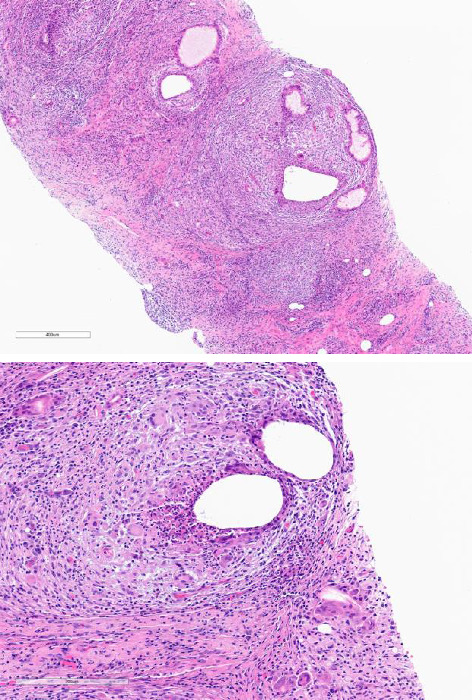

Granulomatous mastitis (GM) is a rare inflammatory condition of the breast that can mimic inflammatory breast cancer. We report a case of a 54-year-old female who developed recurrent GM symptoms in the context of drug-induced hyperprolactinemia, which resolved with dopamine agonist therapy. Our report suggests that serum prolactin should be tested in patients with GM and appropriately managed if elevated.

Abstract Image